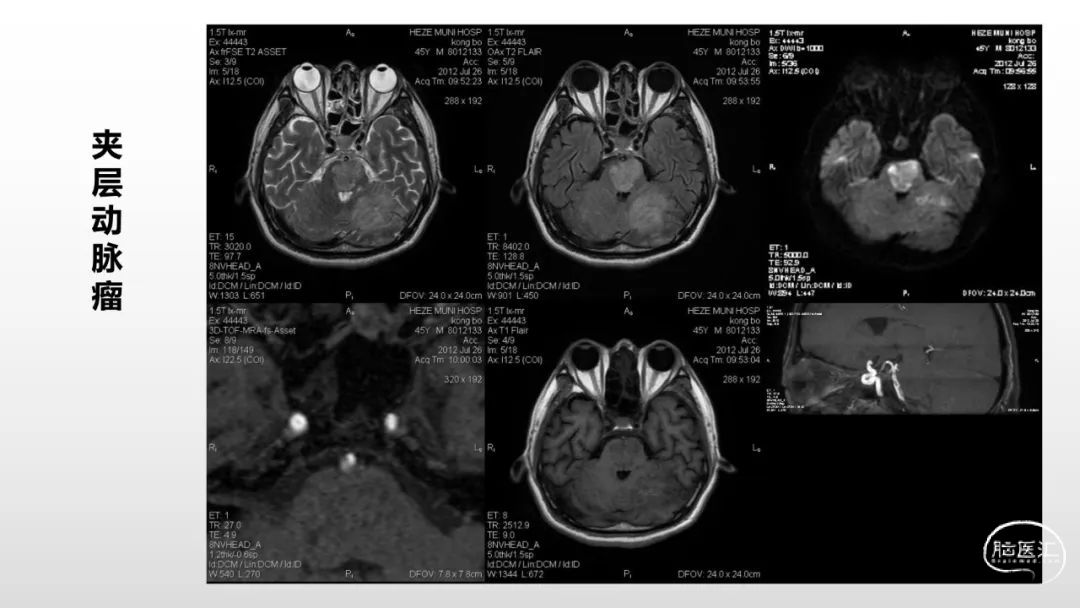

颅脑影像诊断基础知识讲座:《脑血管病》之出血、血管畸形、动脉炎及神经卡压